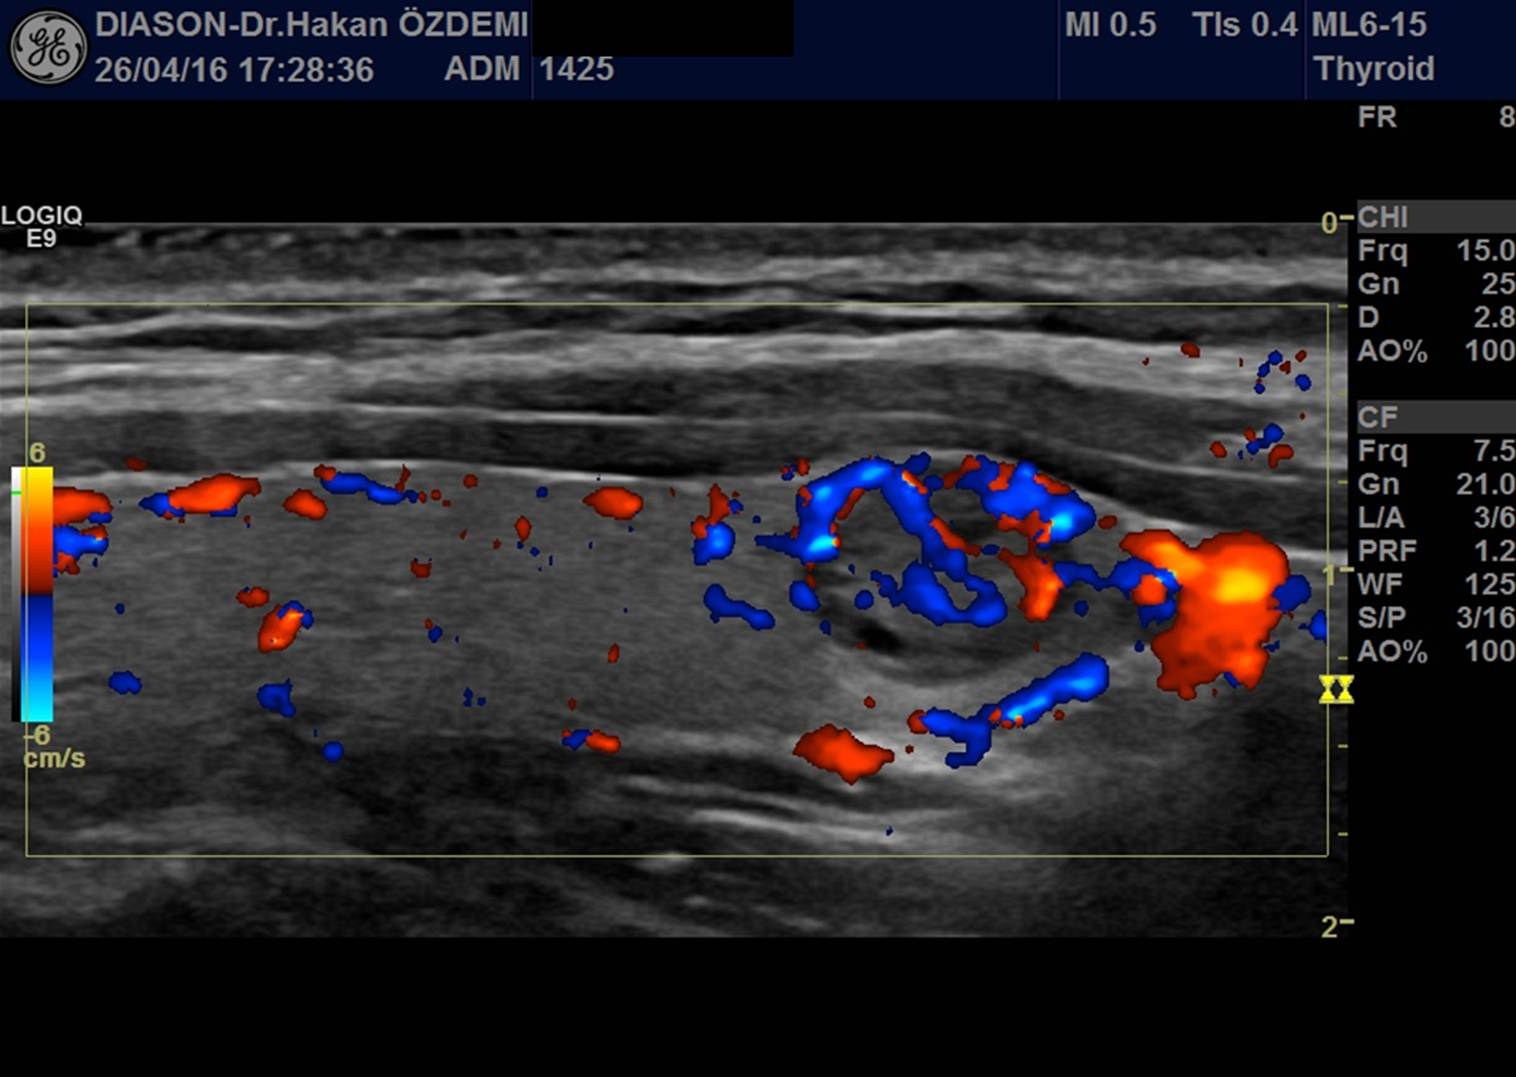

TİROİD BEZİ RENKLİ DOPPLER ULTRASON

Tiroid bezi damarları incelenir.